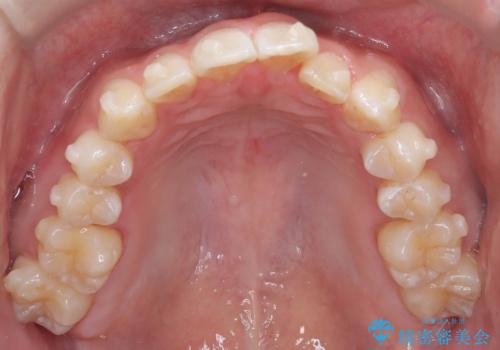

- 歯のデコボコと過蓋咬合を主訴に来院された患者様です。

アーチの拡大とIPRを行い非抜歯で治療を行いました。

歯を抜かずに叢生(デコボコ歯列)と過蓋咬合を改善する事が出来ました。